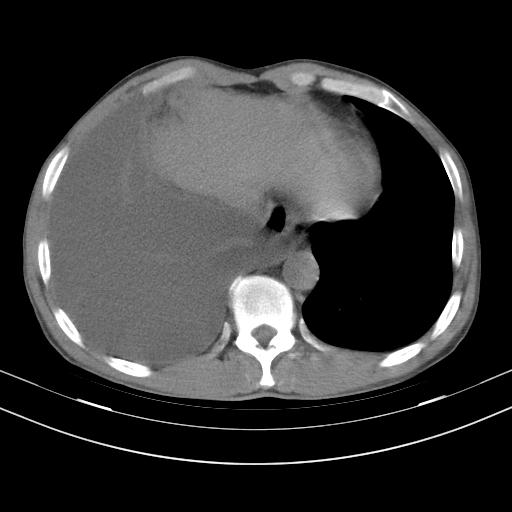

男性,44岁,结核病史多年。现胸闷气短,咳嗽,偶咳血。

右侧胸腔积液

右肺下叶不张

双肺多发结节影最分空洞形成考虑占位不除外结核

双肺陈旧性病变

1、右侧大量胸腔积液伴右肺压缩性膨胀不全,建议抽液治疗后复查 2、两肺继发性tb伴空洞形成。

1)两肺继发性肺结核伴空洞形成,左肺多发性结核球。2)右侧大量胸腔积液伴右肺部分膨胀不全。3)纵隔淋巴结肿大。